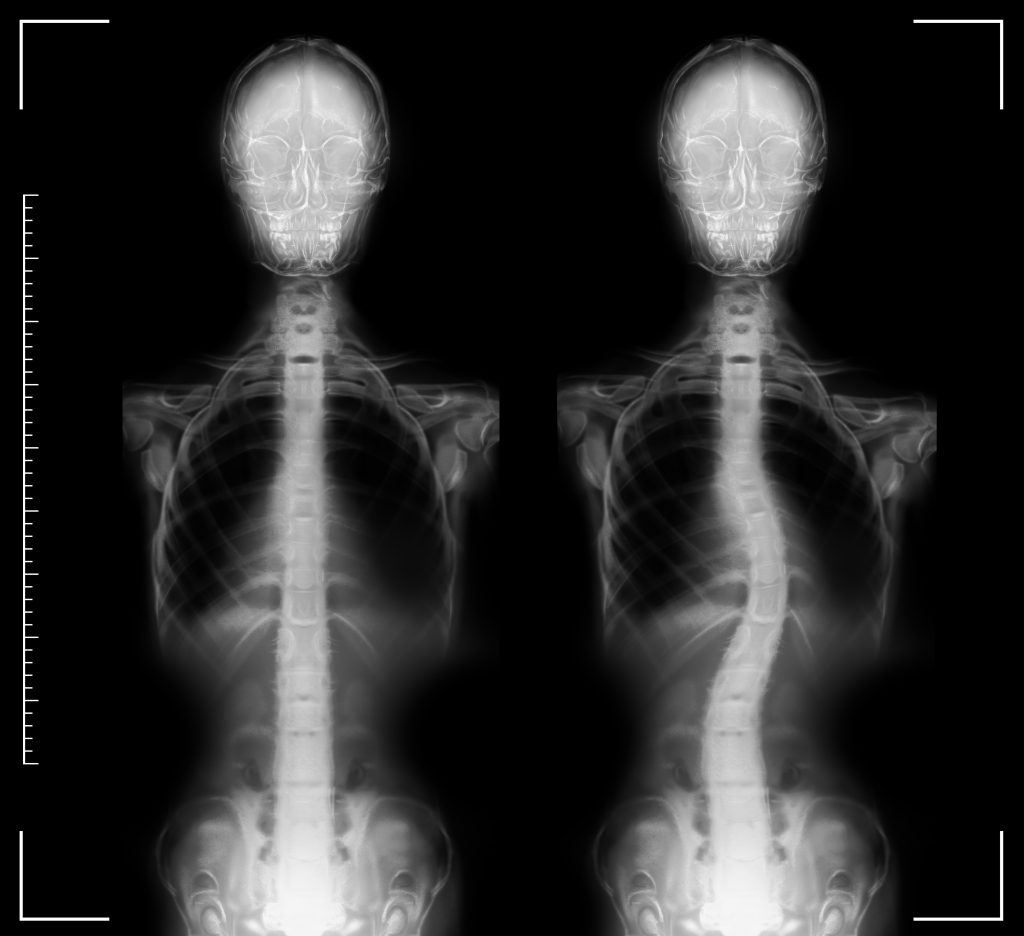

Scoliosis

Scoliosis is a condition where the spine curves and twists, resulting in an S or C-shaped curve. While some cases of scoliosis are mild and may not require treatment, others may require a brace or surgery to correct the curve and prevent further progression. Scoliosis is a complex condition and should be managed carefully.